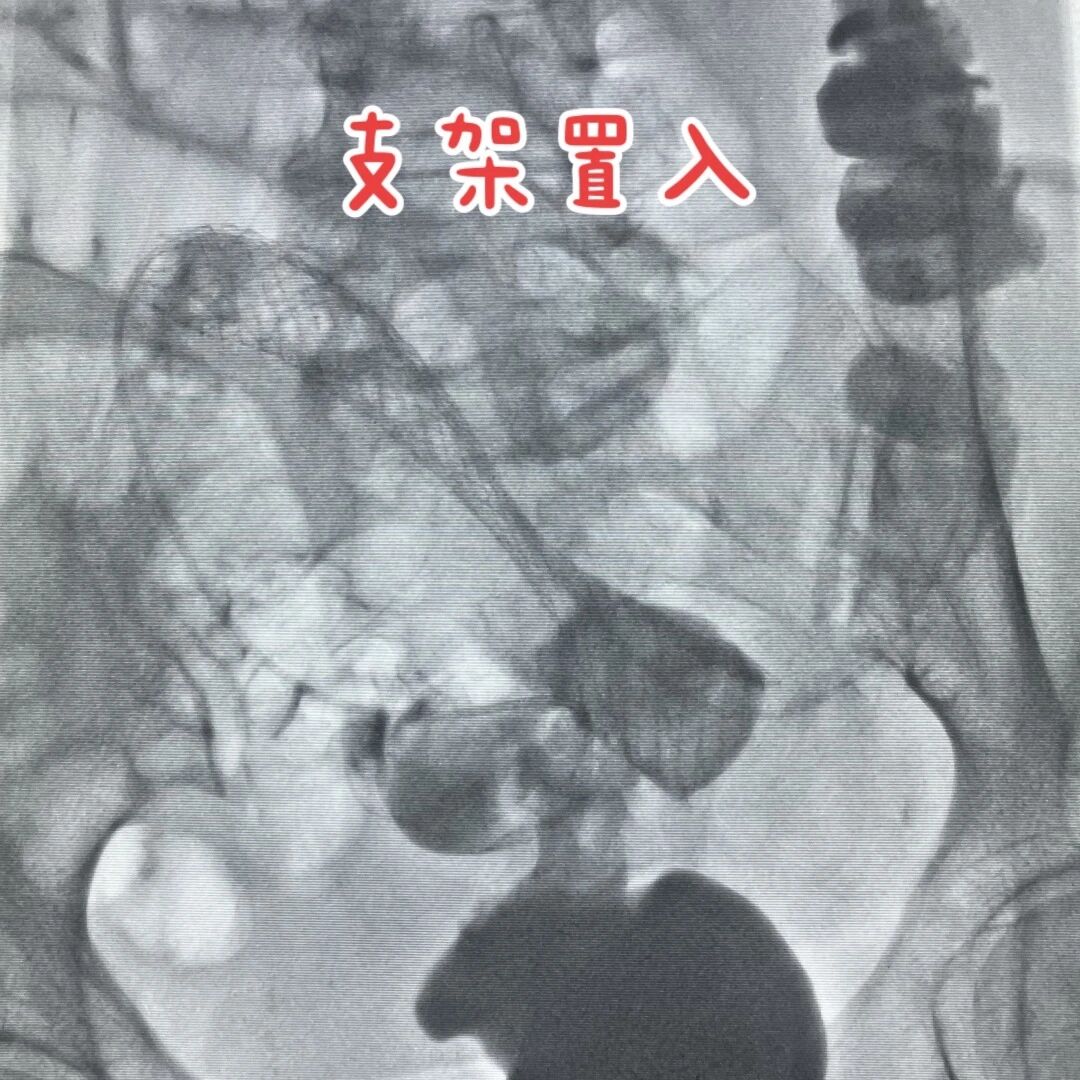

完善術前準備后,徐燕能博士小心翼翼地從肛門把腸道支架送到梗阻點,慢慢撐開來,把堵塞腸道通道重新打開,讓那些被堵住的食物殘渣和氣體能夠順利通過。整個過程約60分鐘,全程全麻,潘婆婆睡了一覺就結束了,一點沒覺得疼。

徐燕能博士介紹,以往治療腸梗阻一般需開腹造瘺,也就是術后要在腹部掛一個糞袋,不僅影響患者生活質(zhì)量和心理健康,還可能出現(xiàn)感染、吻合口漏等并發(fā)癥。但腸道支架不用開腹,恢復快,既能暫時緩解晚期病人的痛苦,還能給需要手術的病人爭取準備時間,把急診手術變成“擇期手術”,讓病人少遭罪。